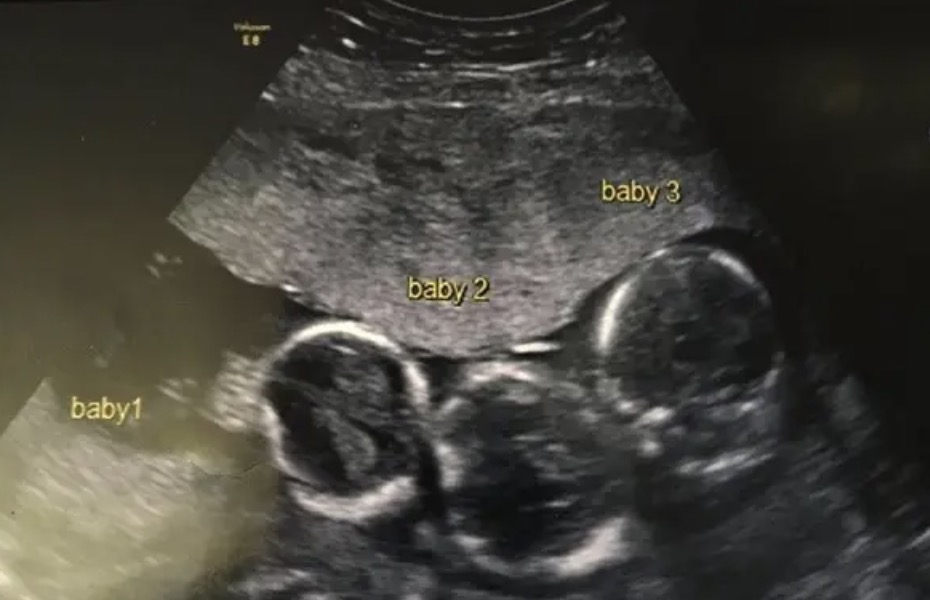

Early in her pregnancy, Becki-Jo got quite sick and had severe headaches. The doctors scheduled her ultrasound earlier than usual, which is when the couple learned the shocking news: she was expecting triplets.

Becki was suffering early on in the pregnancy from very bad headaches. This is when the doctor decided to bring her in for an early ultrasound and this is when she discovered she would be having triplets.